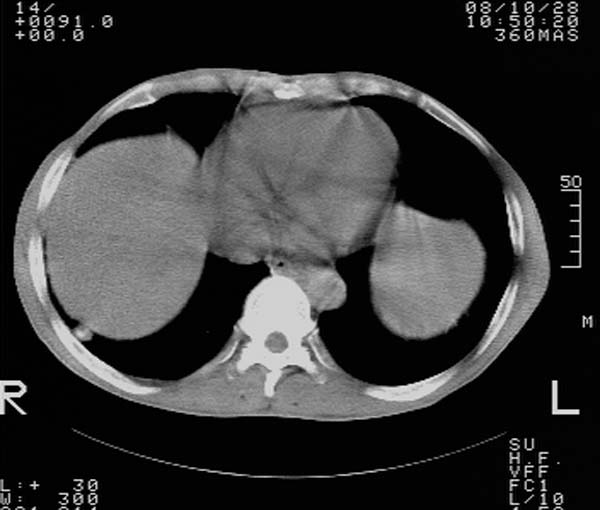

纵隔内及腹膜后广泛淋巴结肿大,脾大,肝内似可见低密度影,结合病史半年前发现颈小结节,逐渐增多增大,现双侧耳后、颌下及颈部表浅淋巴肿大。考虑淋巴瘤。

纵隔,双肺门腹膜后多发淋巴结重大,非融合,肝脾轻度肿大,双肺野弥漫性小结节;考虑淋巴瘤,结节病可能性

纵隔内,双肺门、腋窝及腹膜后多发肿大淋巴结影,肺内小结节影,肝脾体积增大,支持淋巴瘤。肝内多发低密度影,考虑小囊肿。

考虑淋巴瘤肺、肝内转移,脾脏肿大。

纵隔内,双肺门、腹膜后多发肿大淋巴结影及颈部淋巴结肿大,肝脾体积大.结合临床,淋巴瘤可能性大。